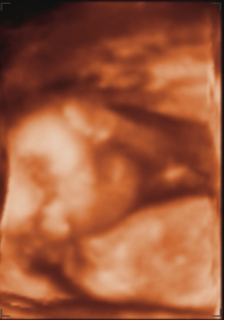

Et voila sa bouille :)

• bébé 16 sa 6.png

bébé 16 sa 6.png

28.4 KB · Affichages: 68